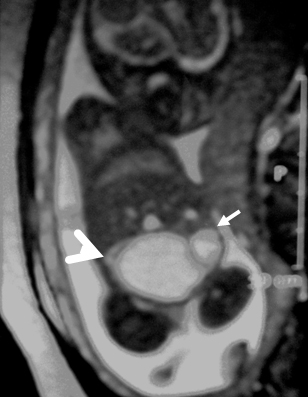

A 26-year-old pregnant women, gravida 1, para 0, was admitted to our prenatal diagnosis centre for detailed ultrasonography examination. Obstetric history was unremarkable. A single fetus was detected at 26 gestational weeks. A presacral located cystic mass measuring 45 × 55 × 40 mm was seen on ultrasound examination (Fig. 1). On doppler ultrasound, the cystic structure with both umbilical arteries around was considered an enlarged distally obstructed fetal bladder initially (Fig. 2). However, the bladder was later identified more superiorly. The amniotic fluid index was 129mm. Diagnosis of the cystic mass was unclear and a fetal MRI was performed, which delineated a large cystic mass with minimal internal echogenicity area, the type IV teratoma (big arrow head). The white arrow demonstrates a cystic mass considered as a hydrometrocolposis (Fig. 3).

Figure 2: The cystic structure with both umbilical arteries around. |